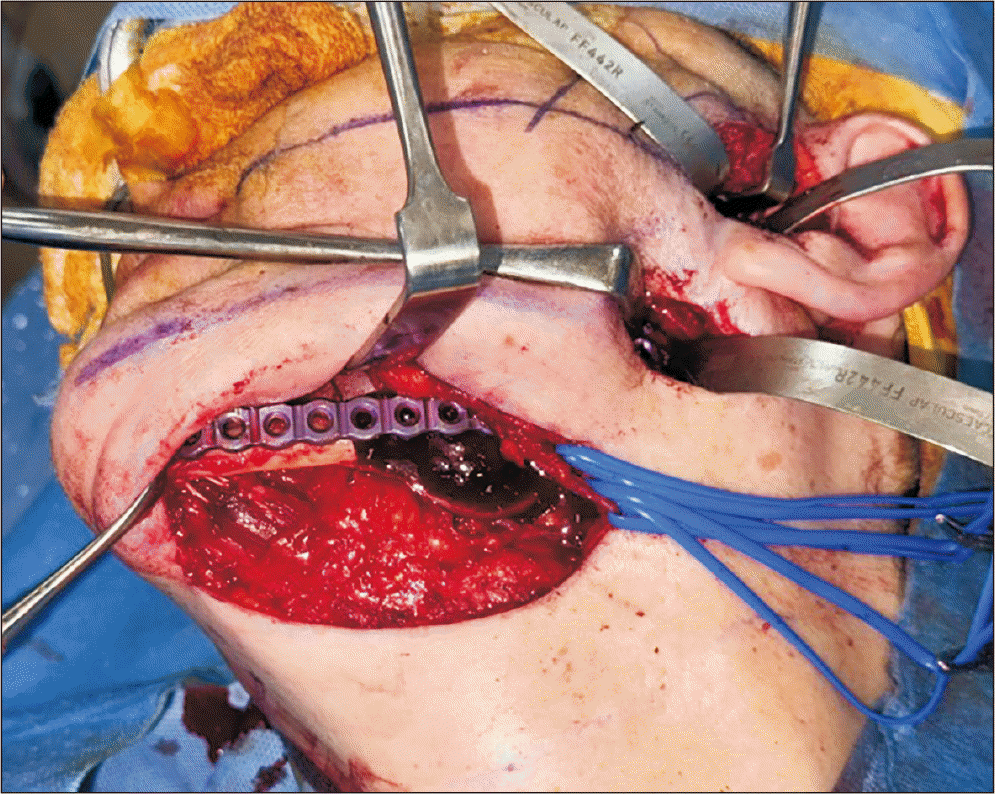

Finally, a submandibular incision was performed approximately 3 cm below the inferior mandibular border, parallel to the relaxed skin tension lines. Dissection proceeded through the skin, subcutaneous tissue, superficial cervical fascia, platysma, and deep cervical fascia. The mandibular plane was approached by carefully detaching the muscles inserted at the basilar border, followed by subperiosteal elevation and skeletal exposure. The facial artery and the marginal mandibular branch of the facial nerve were identified and retracted with vascular loops (Fig. 5), providing safe access for the osteotomy and tumor resection, which were performed using a reciprocating saw and piezoelectric instruments. Primary reconstruction of the mandibular defect was then achieved.

Tunneling was established by a subcutaneous and subperiosteal route connecting the endaural and retromandibular incisions, while preserving a narrow cutaneous pedicle over the bifurcation zone of the facial nerve trunk. The submandibular approach was subsequently connected to this tunnel along the mandibular border, creating a continuous anatomical corridor from the condylar neck to the mandibular body.(Fig. 5, 6) This configuration allowed for continuous visualization of the mandibular bone, minimized traction, and facilitated the perpendicular placement of osteosynthesis screws through the same surgical field.

Fig. 2

Postoperative three-dimensional reconstruction of left mandibular resection and positioning of osteosynthesis system with acrylic spacer. A. Lateral view. B. Frontal view. C. Caudal view.